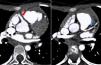

To confirm the diagnosis, CTA was performed, which showed the left main coronary artery originating from the left lower aspect of the MPA, about 10 mm from the aortic root (Figures 2 and 3). This distance raised doubts concerning the feasibility of direct implantation of the LCA into the aorta. The patient's periods of higher heart rate despite negative chronotropic medication and motion-induced artefacts meant that only the proximal portions of the coronary arteries could be defined.

64-slice ECG-gated computed tomography, curved multiplanar reformatting, showing the left main coronary artery originating from the lower left aspect of the main pulmonary artery. The left main coronary artery has a caliber of 2.6 mm and a length of around 3 mm, with regular contours and preserved patency. It presents a normal bifurcation into the anterior descending artery (A) and circumflex artery (non-dominant) (B). These vessels have preserved patency in their visible portions (proximal half).